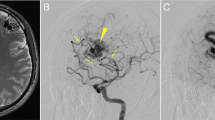

Cerebral cavernous malformations (CCMs) are a neurovascular anomaly that may occur sporadically or be inherited due to autosomal dominant mutations in KRIT1, CCM2 or PDCD10 (refs. 1,2,3,4). Individual lesions are caused by somatic mutations that have been identified in KRIT1, CCM2, PDCD10, MAP3K3 and PIK3CA5,6,7,8,9,10,11. However, the interactions between mutations and their relative contributions to sporadic versus familial cases are unclear. We show that mutations in KRIT1, CCM2, PDCD10 and MAP3K3 are mutually exclusive but may co-occur with mutations in PIK3CA. We also find that MAP3K3 mutations may cause sporadic but not familial CCM. Furthermore, we find identical PIK3CA mutations in CCMs and adjacent developmental venous anomalies (DVAs), a common vascular malformation frequently found in the vicinity of sporadic CCMs12,13,14. However, somatic mutations in MAP3K3 are found only in the CCM. This suggests that sporadic CCMs are derived from cells of the DVA that have acquired an additional mutation in MAP3K3.

Snellings, D.A., Girard, R., Lightle, R. et al. Developmental venous anomalies are a genetic primer for cerebral cavernous malformations. Nat Cardiovasc Res 1, 246–252 (2022). https://doi.org/10.1038/s44161-022-00035-7